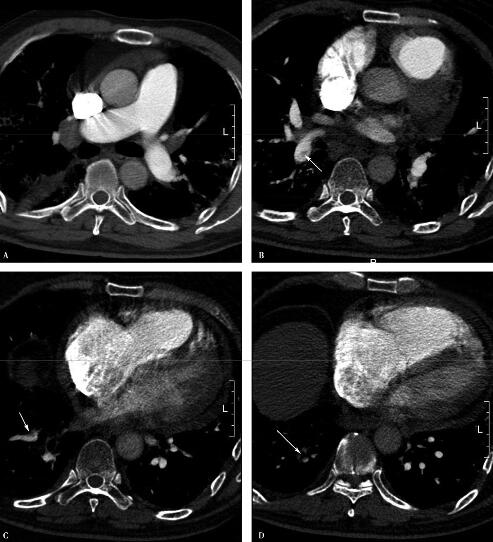

肺动脉CTA(2011年1月13日):右下肺动脉栓塞,心包积液(图3)。

图3

补充上述临床资料后,诊断思路明朗起来。明确诊断为:间质性肺疾病、肺炎、右肺下动脉栓塞。